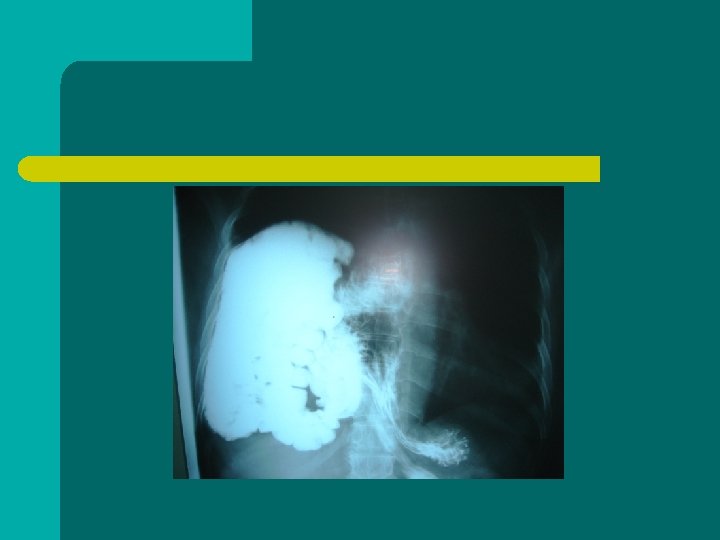

Hernias diafragmaticas l Debilidades naturales: bockdalet y morgani. l Congenitas l Adquiridas: por trauma abierto o cerrado Mas fc lado izq. Lado der. peor pronostico l

sintomatologia l Trastornos respiratorios. l Trastornos abdominales ( ABDOMEN AGUDO)

DIAGNOSTICO l l Historia clinica Gabinete ( Rx, levin, tomografia )

Diagnostico